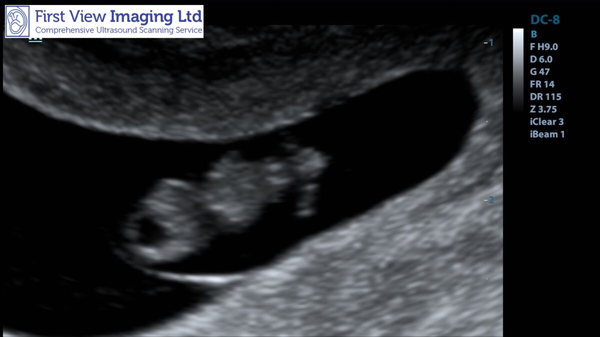

UntilTheVeryEnd · 18/09/2018 17:46

Everyone meet my little bean! A perfect 8 + 1 and lovely little heartbeat 💗 so emotional today...can’t believe it’s actually real.

@UntilTheVeryEnd yippee! That's super exciting!!!! I'm slightly envious but very excited for you!!! I love a good bean pic! (and now for the gossip, did they get that from an external scan or did they have to go internal?)

@UntilTheVeryEnd lovely scan. How exciting!!!

How exciting @UntilTheVeryEnd!! So glad the scan went well Smile

MynameisJune · 18/09/2018 18:16

@untiltheveryend fabulous pic! So glad everything is well.

Thanks everyone! We are just delighted.

@frankiefumbles pleased to say that it was an external scan and picked up straight away. Needed to have a crazy full bladder tho - a touch uncomfy.

Lovely news and a beautiful picture @UntilTheVeryEnd.